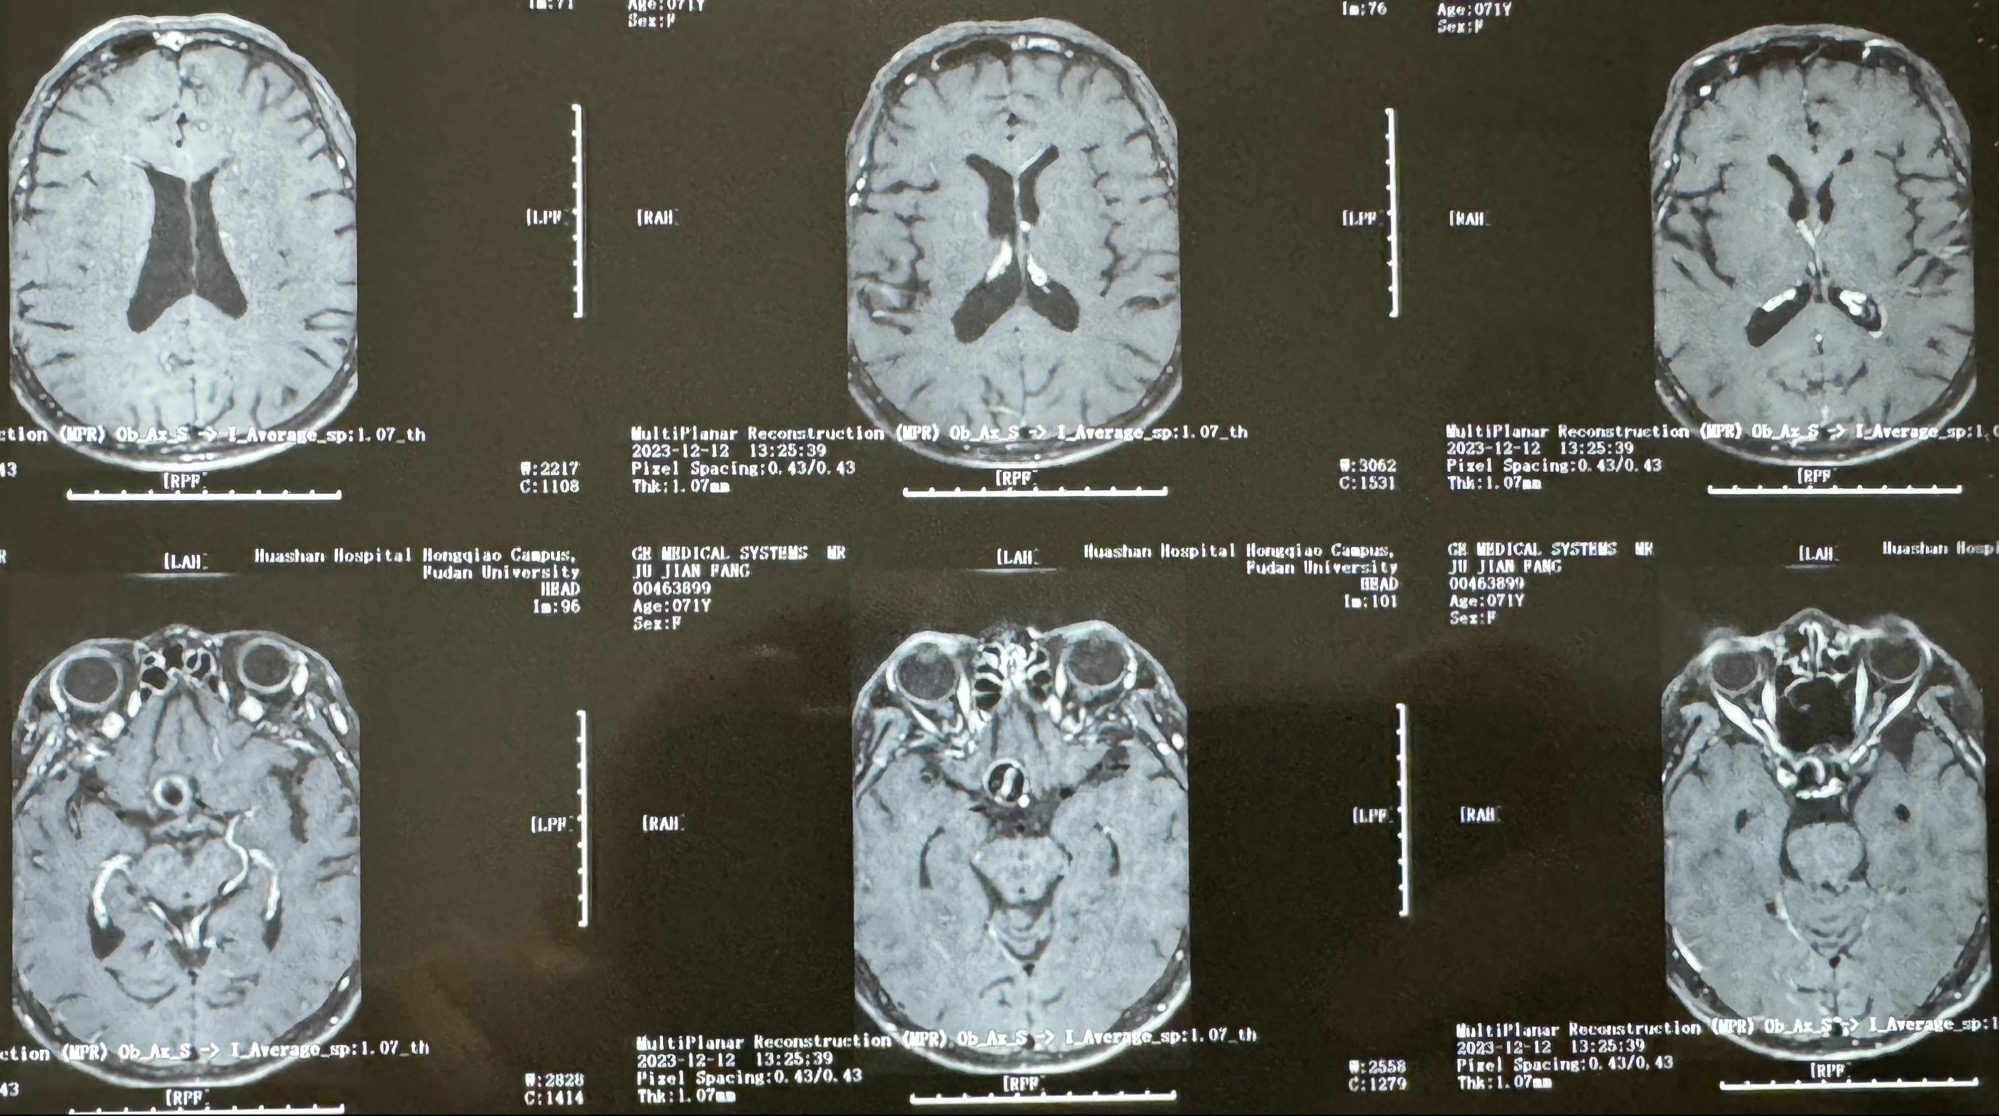

辅助检查;2023-11 外院 头颅MRI+MRA:左侧颈内动脉C6段动脉瘤;

2023-12-12MRI